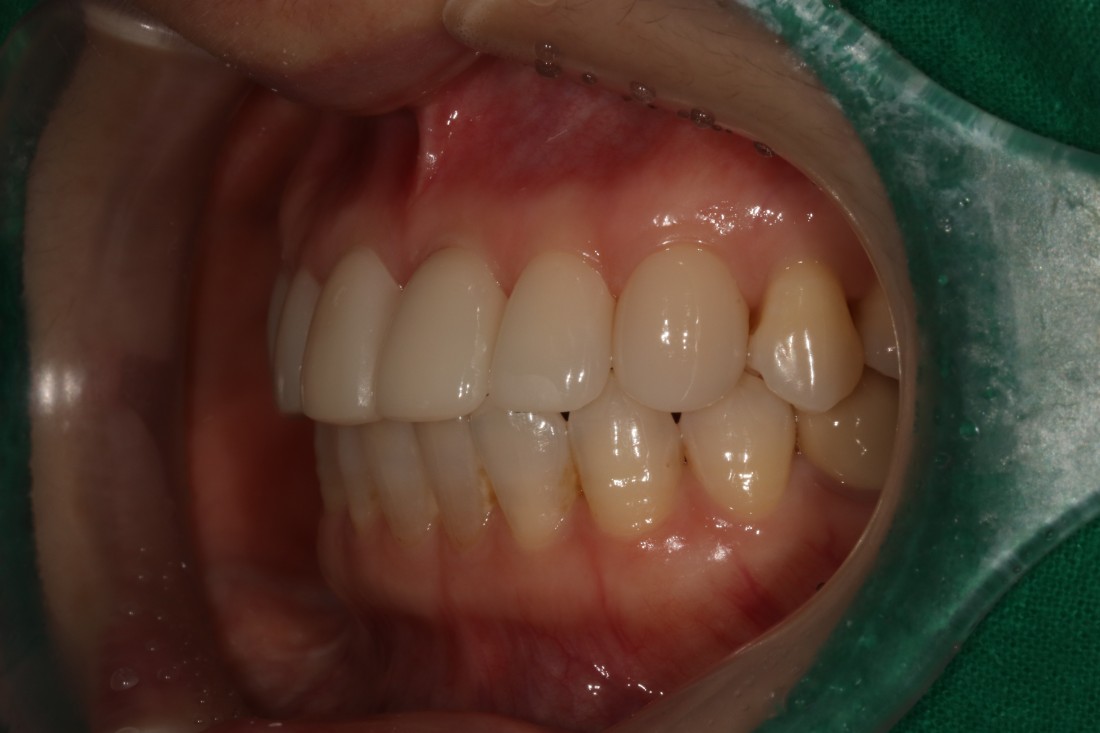

누가봐도 라미네이트 한 것 같은

뭉툭하고 새하얀 치아가 아니라,

광주 무삭제 라미네이트 치과는

'자연스러운 아름다움'을 추구합니다.